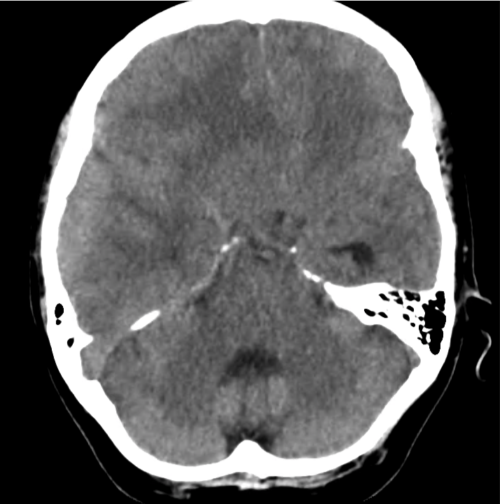

ct-mass_07 – Differential Diagnosis of

This visual representation further underscores the significance of context in interpreting CT images. The potential implications of the findings can drastically alter patient management. Sophisticated algorithms now complement the human touch, ensuring that subtle details are not overlooked in this vast ocean of data.

CT Abdomen showing mass

The final image rounds out this exploration into the world of CT scans illuminating the abdomen. The revelation of masses within this realm leads to profound challenges in patient care. Each scan not only enhances clinical knowledge but also reshapes treatment paradigms, offering hope for innovative therapeutic avenues.